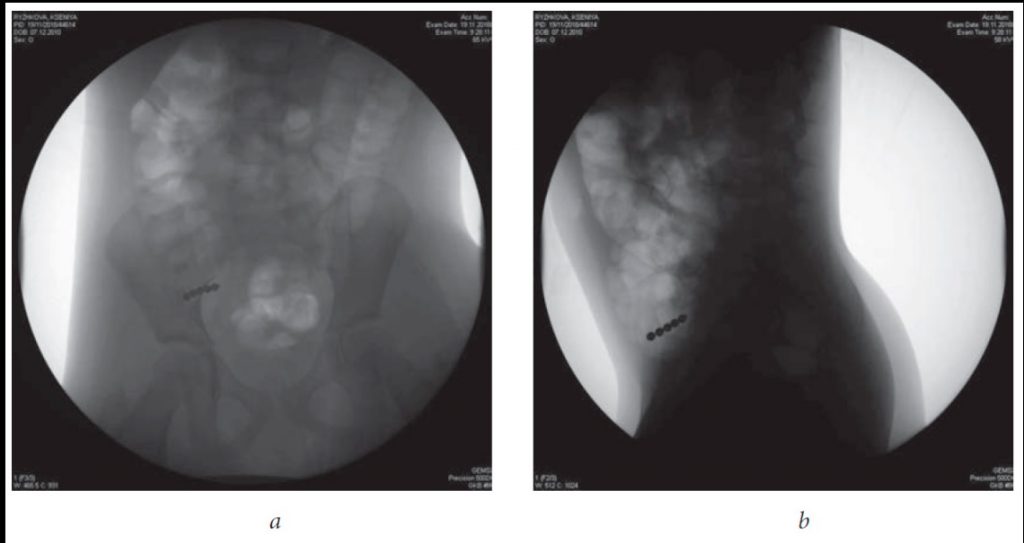

Инородные тела металлической плотности